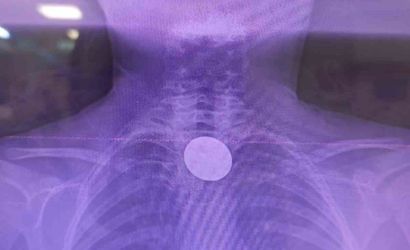

Siirt'te 8 yaşındaki Y.K., boğazına değeri 5 lira olan bir madeni para kaçması sonucu hastaneye başvurdu. Siirt Eğitim ve Araştırma Hastanesi'nde yaşanan bu olay, doktorların hızlı müdahalesi sayesinde başarılı bir şekilde sonuçlandı.

Yabancı Cisim Yutma Gerçeği

Ailesi tarafından hastaneye getirilen çocuk, yabancı cisim yutma şikayeti ile acil servise alındı. Yapılan detaylı incelemeler sonucunda, madeni paranın yemek borusuna kadar ilerlediği belirlendi. Uzman ekip, gastroenteroloji doktoru Dr. Yaren Dirik ve kulak burun boğaz hekimi Yasin Gökçınar tarafından gerçekleştirilen operasyonla para çıkarıldı.